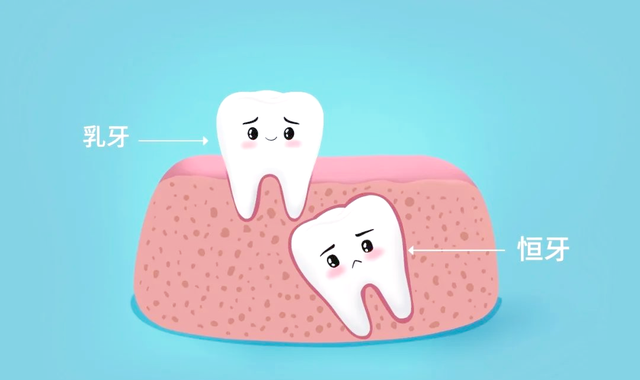

双排牙,并不是新物种。普通乳齿没掉,恒牙又迫不足待顶出来,就像地铁上硬挤上来的乘客,空间有限,步骤全乱。

父母大意之处,领先是对乳齿“寿命”的误判。许多东谈主以为乳齿当然掉落是天经地义,殊不知,乳齿淹留,是双排牙的头号帮凶。

乳齿床部按理说应该被恒牙渐渐接纳,像秋天的落叶当然零星,但一朝接纳失败,乳齿不知廉耻地不愿走,恒牙惟有匠心独具。

更扎心的是,不是所有这个词双排牙都能靠等。特地是下门牙区域,恒牙萌出力量大,所在却偏,收缩驰松就能把牙列挤成怪形势。